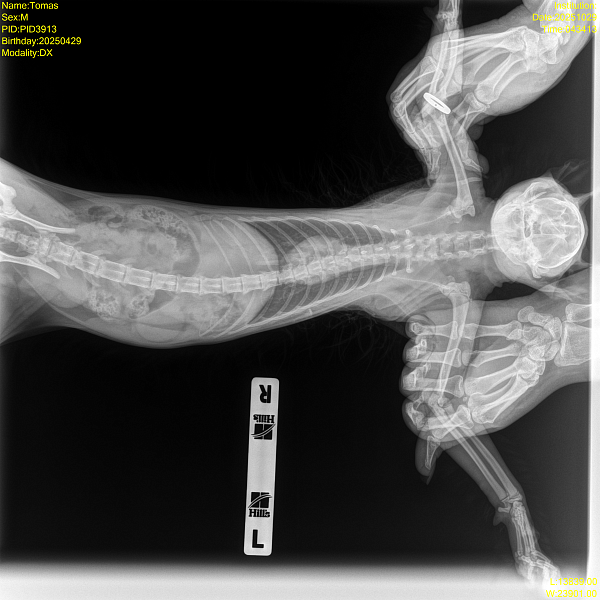

Рентген - смотрел кардиолог, сказал ничего патологического не видит, но может лучше показать пульмонологу для второго мнения.

Прикладываю заключение узи, рентген и видео.

Здравствуйте, дыхание с открытым ртом у кошек при активной физической активности и сильном беспокойстве это может быть вариантом нормы, а вот кашель нет. Наиболее частые причины кашля у кошек это бронхит и астма, дифференцировать эти состояния по рентгену невозможно. Если приступы кашля становятся частыми, то для уточнения диагноза назначают дополнительную диагностику - КТ грудной полости, бронхоальвеолярный лаваж. Если нет возможности провести такую диагностику, то начинаются эмпирическую терапию, чаще всего с ингаляций.

на Ваших снимках выраженных изменений в грудной полости нет, но нельзя исключать, что при сохранении симптомов особенно в виде кашля изменения появятся со временем, если речь идет о формирующейся хронической проблеме. Поэтому если кашель сохраняется, то снимок нужно повторять через 2-6 месяцев.